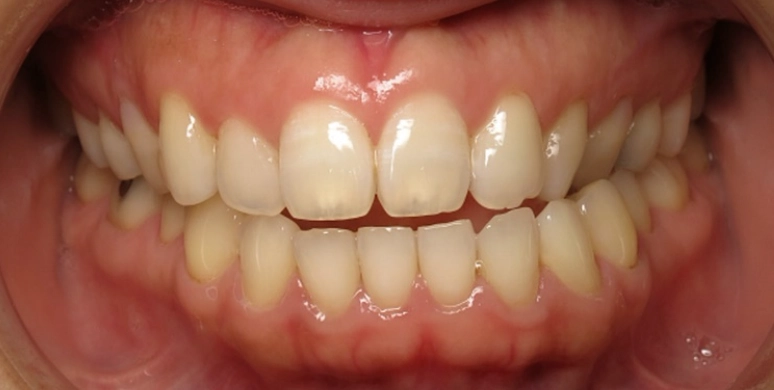

Before

After

Patient treated with EXPANSION and braces